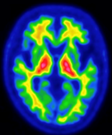

日本メジフィジックス株式会社 様

画像提供:東京都健康長寿医療センター 認知症未来社会創造センター 副センター長 石井 賢二 先生 提供

アミロイドβプラークが溜まっている場合(陽性)

認知症の原因がアルツハイマー病である可能性が高くなります。

ただしアミロイドβプラークが溜まっていてもアルツハイマー病による認知症になるとは限りません。アルツハイマー病以外の認知症や正常な高齢者にもアミロイドβプラークが溜まる場合があります。アルツハイマー病かどうかは、症状や他の検査結果を併せて、医師が総合的に判断します。